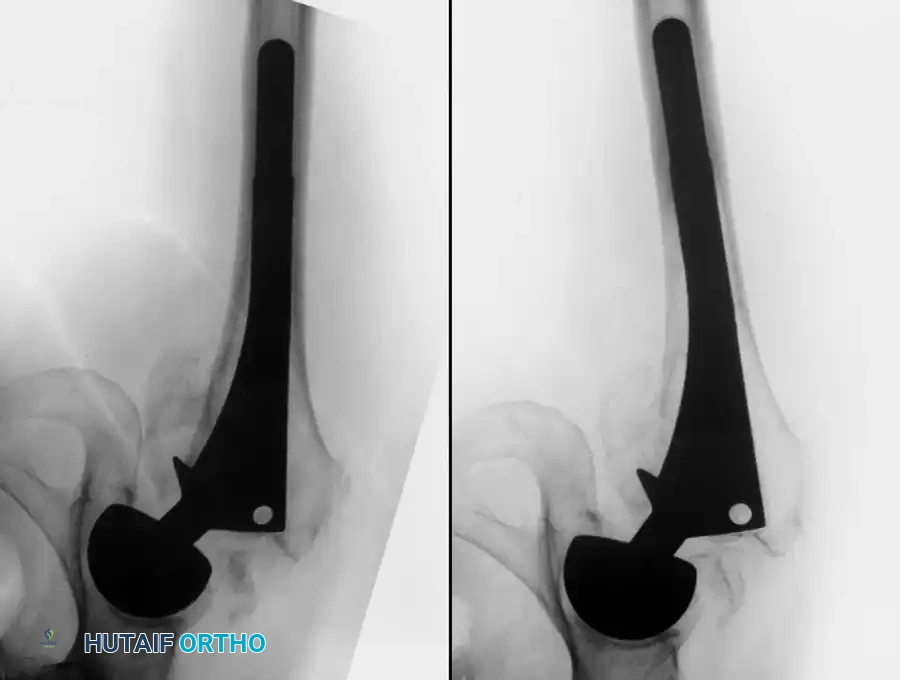

Sagittal Plane Forces and Stem Torsion

Forces on the hip joint do not act exclusively in the coronal plane. Because the body’s center of gravity is posterior to the transverse axis of the hip joint, forces also act in the sagittal plane, creating a bending moment that deflects the stem posteriorly.

These posterior deflecting forces are magnified when the loaded hip is flexed—such as when arising from a low chair, ascending or descending stairs, or lifting heavy objects.

Image

During the normal gait cycle, resultant forces are directed against the prosthetic femoral head from a polar angle between 15 and 25 degrees anterior to the sagittal plane of the prosthesis. During stair climbing and straight leg raising, this resultant force shifts even further anteriorly on the head. This eccentric loading causes posterior deflection, or retroversion, of the femoral component.

Brand et al. measured these "out-of-plane" forces at 0.6 to 0.9 times body weight. Because implanted femoral components must withstand substantial torsional forces immediately postoperatively, cementless stems must be designed and implanted to achieve absolute initial rotational stability (press-fit) within the femoral diaphysis or metaphysis. Similarly, the geometry of a cemented implant must impart rotational stability within its polymethylmethacrylate (PMMA) cement mantle.